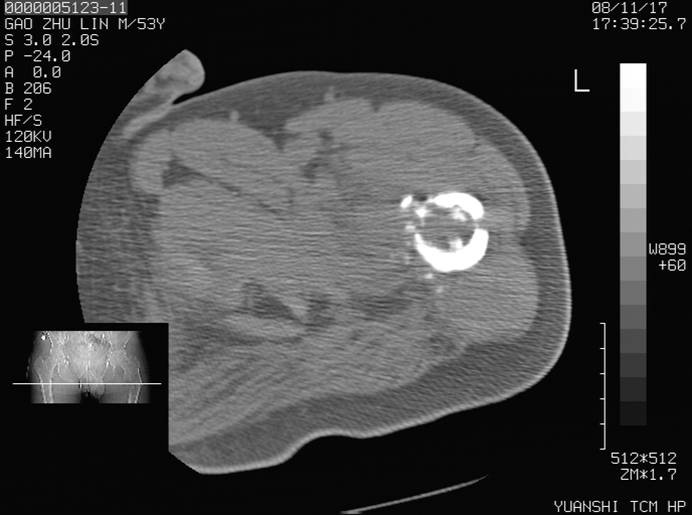

标题: CT16696:M53Y,左股骨上段骨折。 [打印本页]

标题: CT16696:M53Y,左股骨上段骨折。

左股骨上段外伤1个小时,左股骨上段疼痛。村医以腰椎间盘病变给以按摩及理疗数天。

图像不太清楚,左股骨上段外伤性骨折?病理性骨折?

左股骨上段粉碎性骨折

左股骨上段粉碎性骨折;建议上传骨窗看看是不是病理性的啊!

左股骨上段粉碎性骨折,不排除病理性骨折可能。

考虑骨肉瘤伴病理骨折

考虑:骨肉瘤伴病理骨折.

病理性骨折,考虑转移所致.